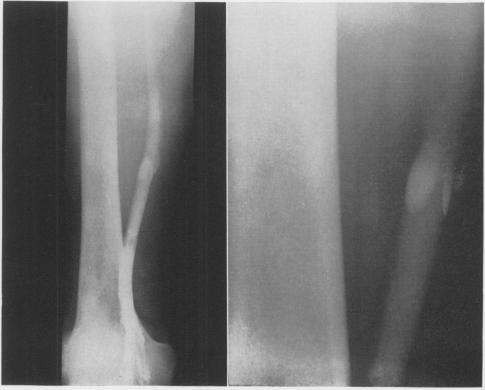

Venous stasis in the lower extremities.

Ann Surg. 1960 Oct;152(4):678-85. doi: 10.1097/00000658-196010000-00011.